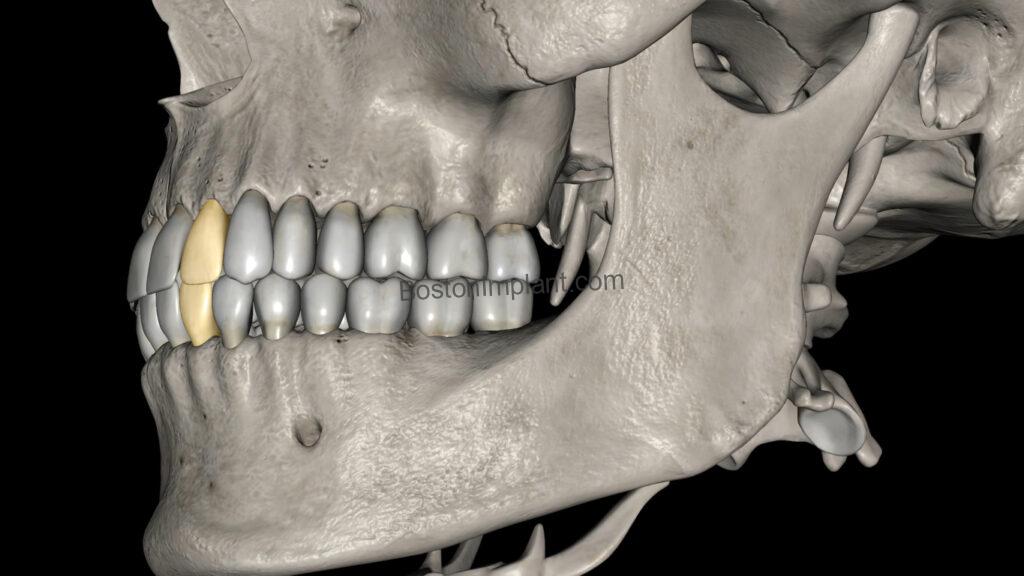

6. Orthodontics (Invisalign, Clear Aligners, Teeth Straightening): This is a newer application for CBCT in dentistry, but Invisalign and clear aligner patients can greatly benefit. In orthodontics, teeth (specifically their roots) move within the bone. Traditionally, we estimated root shapes based on the visible crown. Now, with 3D root and bone images from CBCT, we eliminate guesswork. This allows for more accurate simulation of root movements, ensuring the best possible outcome for your teeth straightening journey.